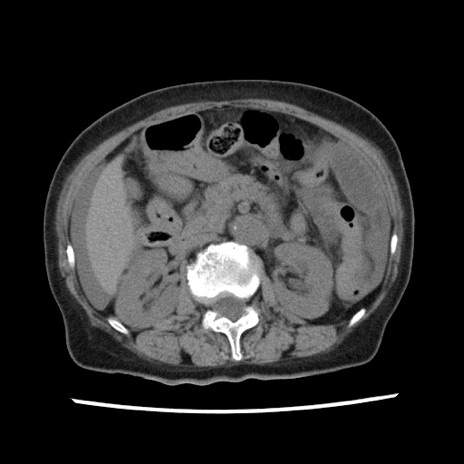

【症例】80歳代女性

【主訴】腹痛

【現病歴】8時間前から腹痛あり来院。

【既往歴】糖尿病、脂質異常症、子宮体癌にて子宮全摘術

【身体所見】意識清明・会話良好だが腹痛で苦悶様、全腹部にわたって反跳痛と圧痛あり

【データ】WBC 13600、CRP 0.14、LDH 224、CK 90